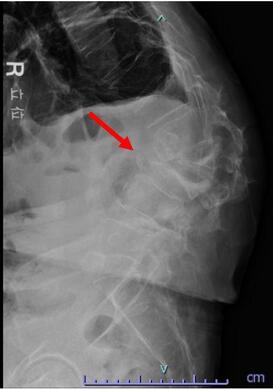

頚椎症性頚髄症

加齢変化による椎間板の膨隆・骨棘(骨のとげ)の変化によって、頚椎の脊柱管の中にある脊髄が圧迫されて頚部や肩の痛み、手足のしびれ、手指の巧緻運動(細かい作業)障害、歩行障害などの症状がでる疾患です。

一般的に日常生活に支障があるような手指の巧緻運動障害、階段昇降に手すりが必要となると脊髄の障害は重症で手術的治療が必要です。

術前MRIでは多椎間で脊髄(灰色)を圧迫しています。後方手術施行後、脊髄への圧迫は改善しています。